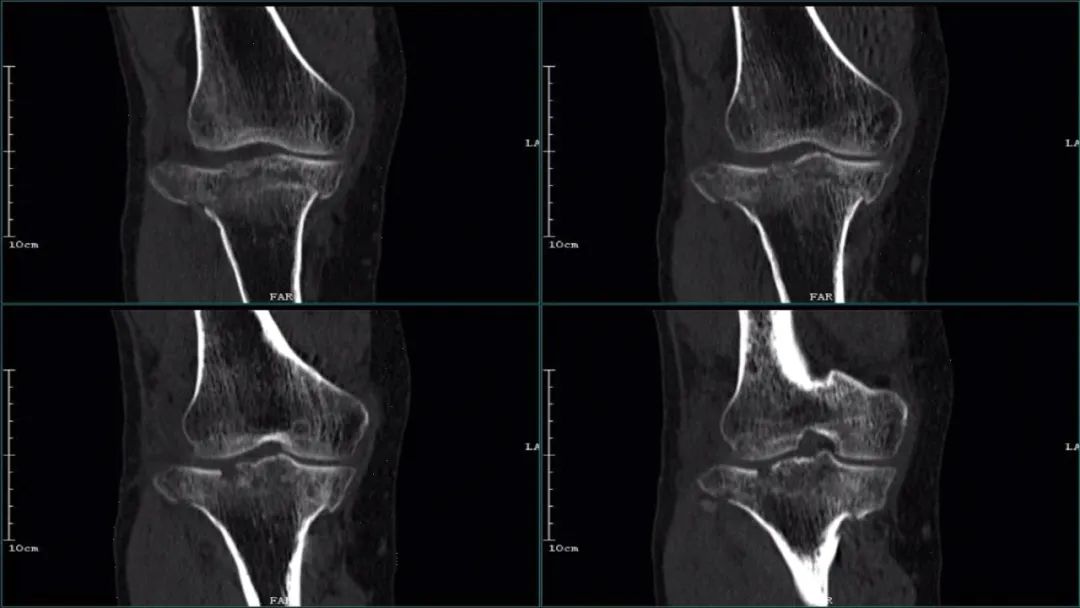

①CT

CT:胫骨外侧平台骨皮质断裂,断端稍移位,无关节面压缩; 医学百科网 | YxBaike.Com

MRI:胫骨外侧平台单纯性劈裂伴骨挫伤。